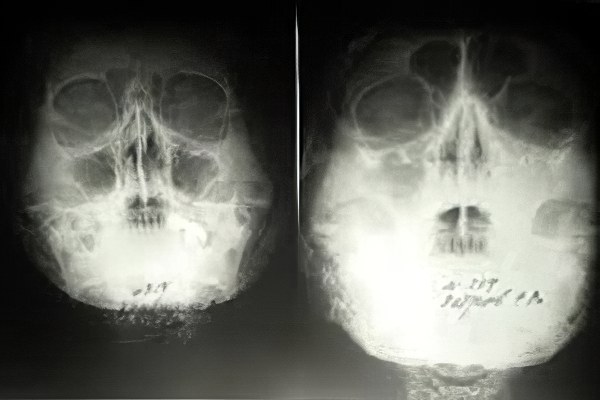

Хронический гайморит — это заболевание с длительным и медленным течением, которое имеет периоды обострений и ремиссий. Оно проявляется частыми головными болями, общим недомоганием и заложенностью носа. Симптомы зависят от степени запущенности воспалительного процесса в поражённых пазухах. Воспаляется верхнечелюстная пазуха, известная как гайморова. Гайморит является одной из форм синусита, поэтому врачи иногда используют термин «хронический максиллярный синусит».

• Травматический гайморит. Развивается из-за нарушений носового дыхания, вызванных травмами черепа.